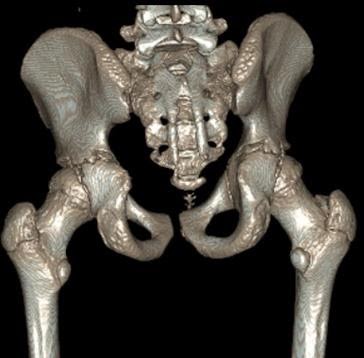

Here is a 13-year-old male footballer with professional aspirations. They developed acute onset left groin pain while sprinting (on the back of a sustained period of increased training intensity), failing to settle several weeks down the line. They had preceding grumbling, but manageable, buttock pain and intermittent clunking.

MRI demonstrated an anterior labral tear, but also lateral acetabular ‘under coverage’. The subsequent CT with 3D reconstruction images (Figs 17 & 18) – the gold standard investigation – shows dysplasia principally of the posterior wall.

Figure 17 CT (anterior view)

Figure 18 – CT (posterior view)